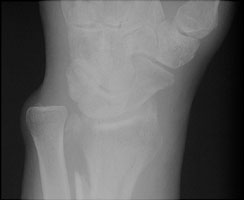

- Click on the image for a larger versionBLateral radiograph of the wrist. Neither fracture is well seen.